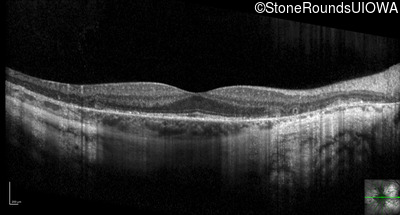

Optical Coherence Tomography - Right - 20/20 -1

Exemplar / OCT Stack